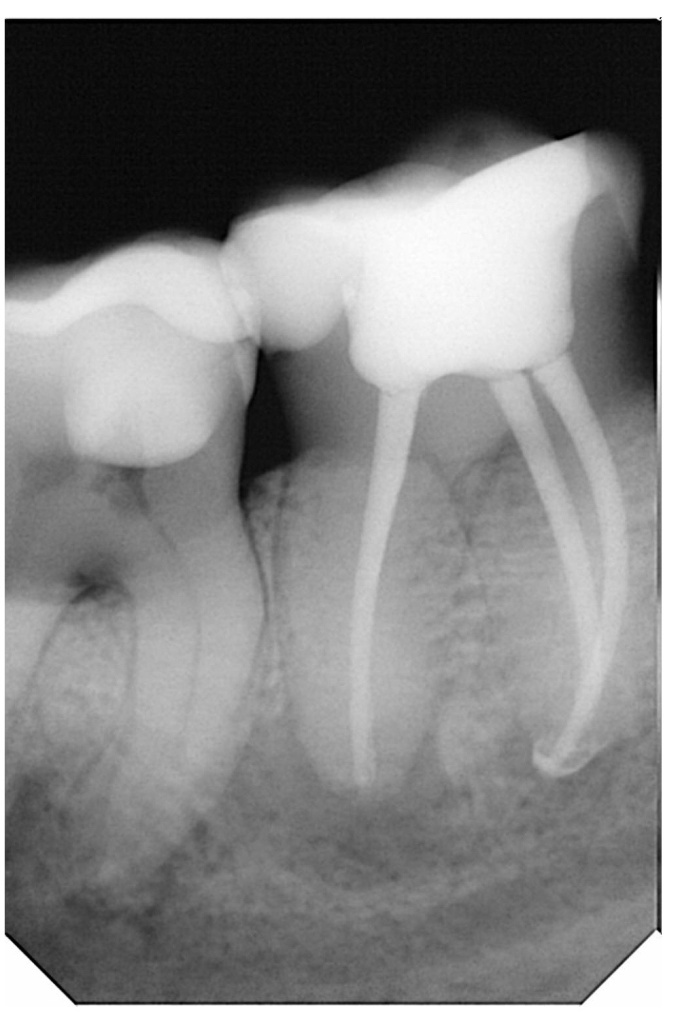

На клинических фотографиях демонстрирующая этапы лечения корневых каналов зуба под микроскопом и с использованием эндомотора.

На фото 1 показано начальное состояние каналов с возможными некротизированными тканями или старым пломбировочным материалом.

4. Контроль качества (фото 3).

- Под микроскопом видна идеально очищенная и сформированная система каналов, готовая к обтурации.

-

Отсутствие остатков дентина, перфораций. На фото 2 показаны полностью распломбированные каналы.

5. Обтурация (фото 4).

Горячая Гуттаперча + силер (термопластический метод вертикальная конденсация ). Более предпочтительный метод обтурации.